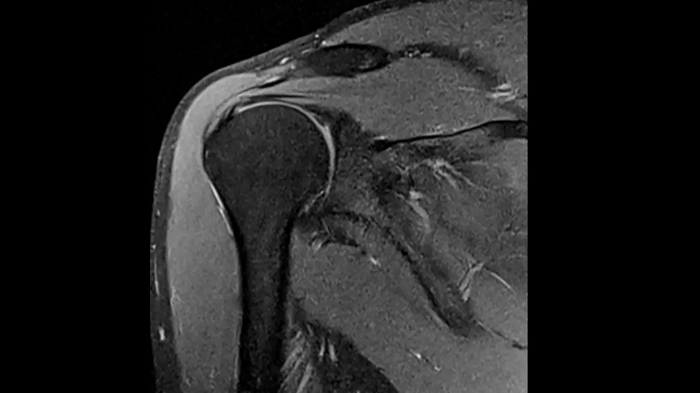

Shoulder

PD TSE Fat Sat with Deep Resolve and Simultaneous Multi-Slice

Exceptional fat suppression and performance for the shoulder’s clear imaging. Integrating the Deep Resolve’s power with the proven Simultaneous Multi-Slice technique.

SMS 2 | Deep Resolve Gain & Sharp

0.4 x 0.4 x 3.0 mm2

TA 3:20 minutes

MAC-ID: 7aaaa0213. Image Credit: Siemens Healthineers